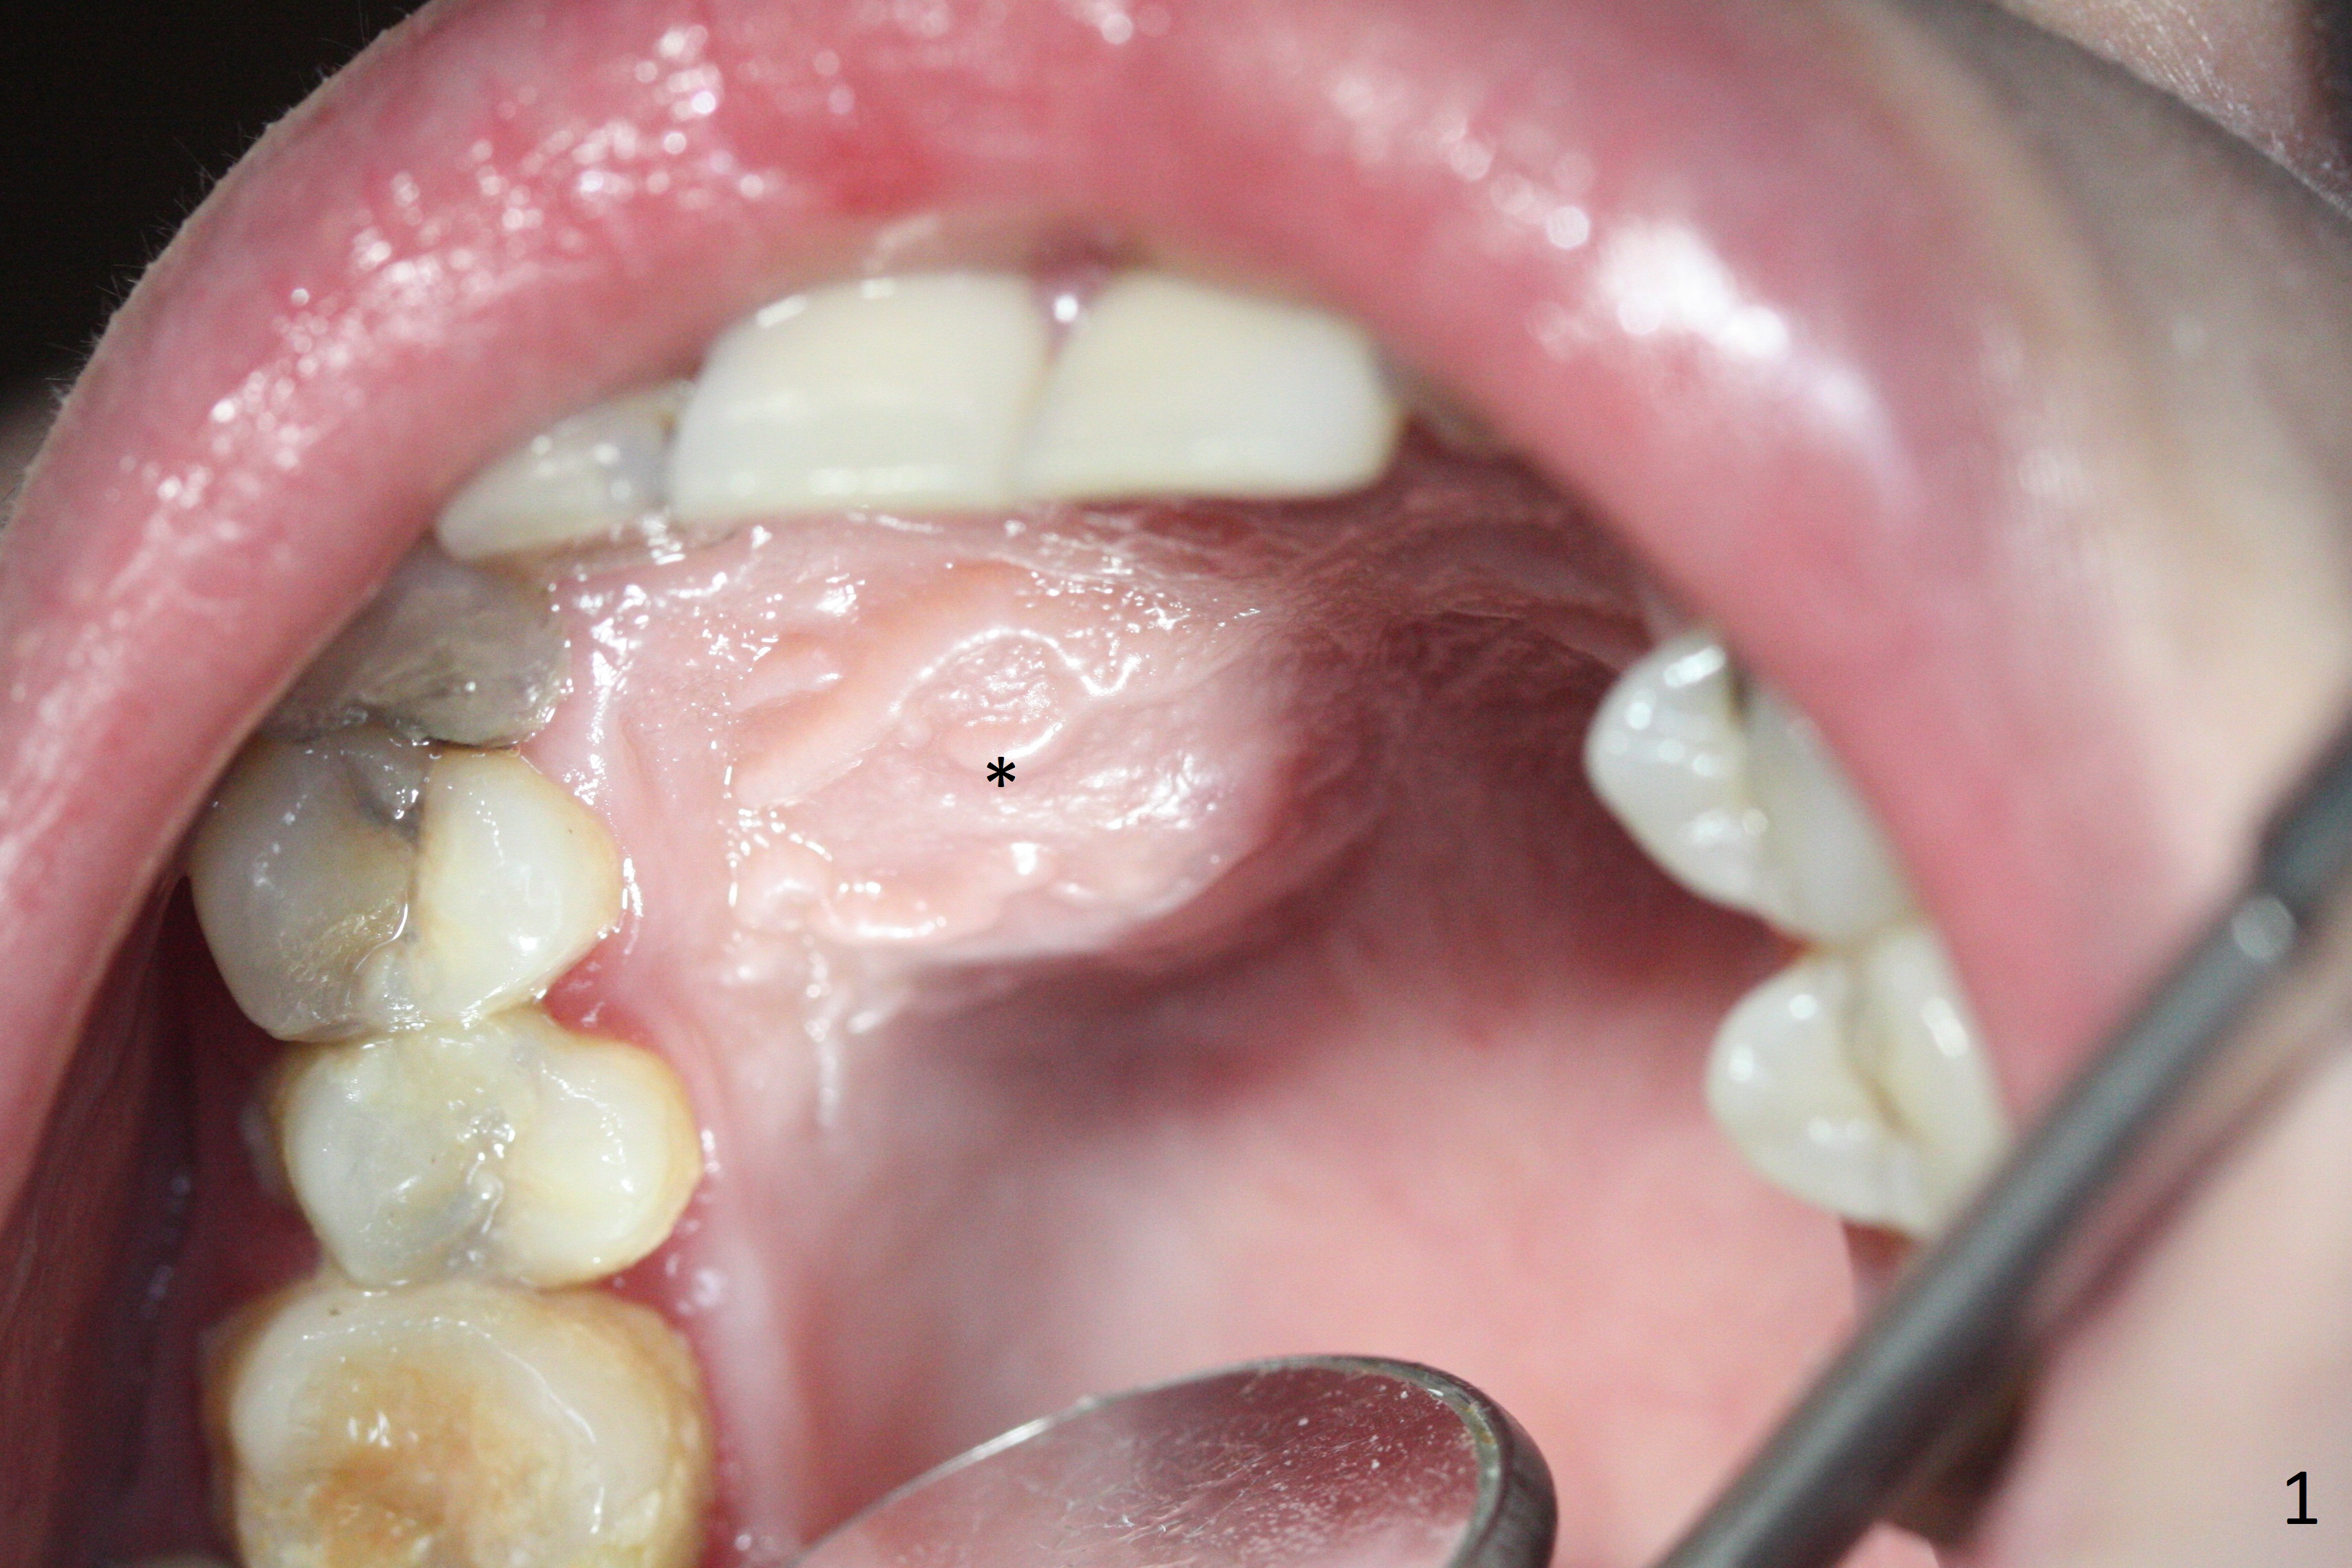

A 30-year-old woman presents to clinic with a large palatal swelling (Fig.1,2). In fact the tooth #7 is necrotic with a periapical radiolucency (Fig.2 arrowheads). RCT is initiated; note the curved canal and file (Fig.3). To reduce the large lesion, Calcium Hydroxide paste is placed in the enlarged canal (Fig.4 *). In a month, the palatal lesion decreases (Fig.5). After re-debridement of the canal, Calcium Hydroxide paste is re-applied.